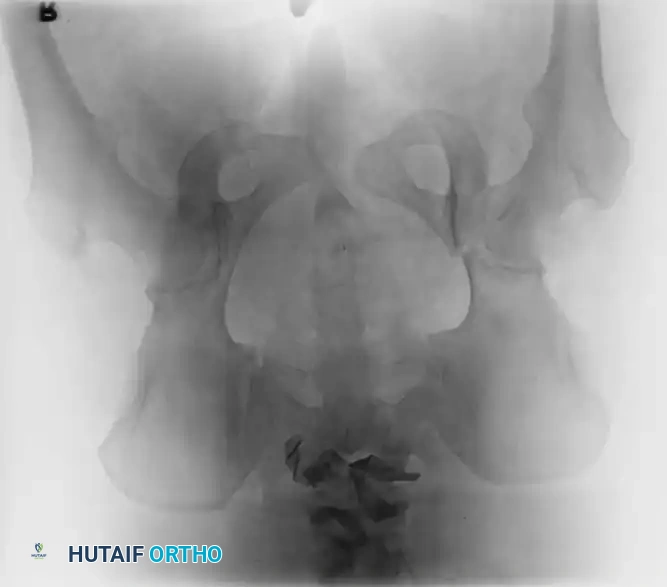

3. Percutaneous Sacroiliac (SI) Screws (Posterior Ring)

The gold standard for posterior ring fixation in appropriately selected patients.

* Indications: Sacral fractures, SI joint disruptions, crescent fractures.

* Technique: Performed under strict fluoroscopic guidance (Inlet, Outlet, and Lateral sacral views).

* Trajectory: The guide wire is advanced from the lateral ilium, across the SI joint, into the S1 (or S2) vertebral body.

* Safety Corridors: The surgeon must possess an intimate understanding of sacral dysmorphism. The "safe zone" is bounded by the sacral neural foramina inferiorly, the spinal canal posteriorly, and the sacral ala anteriorly.

Pitfall: Failure to recognize a dysmorphic sacrum (characterized by upper sacral segment elevation, non-recessed alae, and oblique neural foramina) can lead to catastrophic L5 nerve root injury or vascular penetration during SI screw placement.